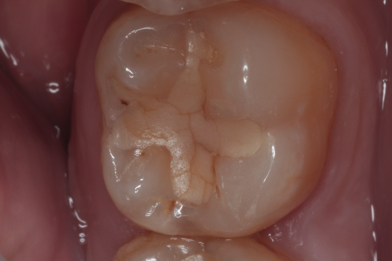

Лечение кариеса на зубе 37, 36 «скрытая кариозная полость на зубе 36»

Колиш Максим Петрович -